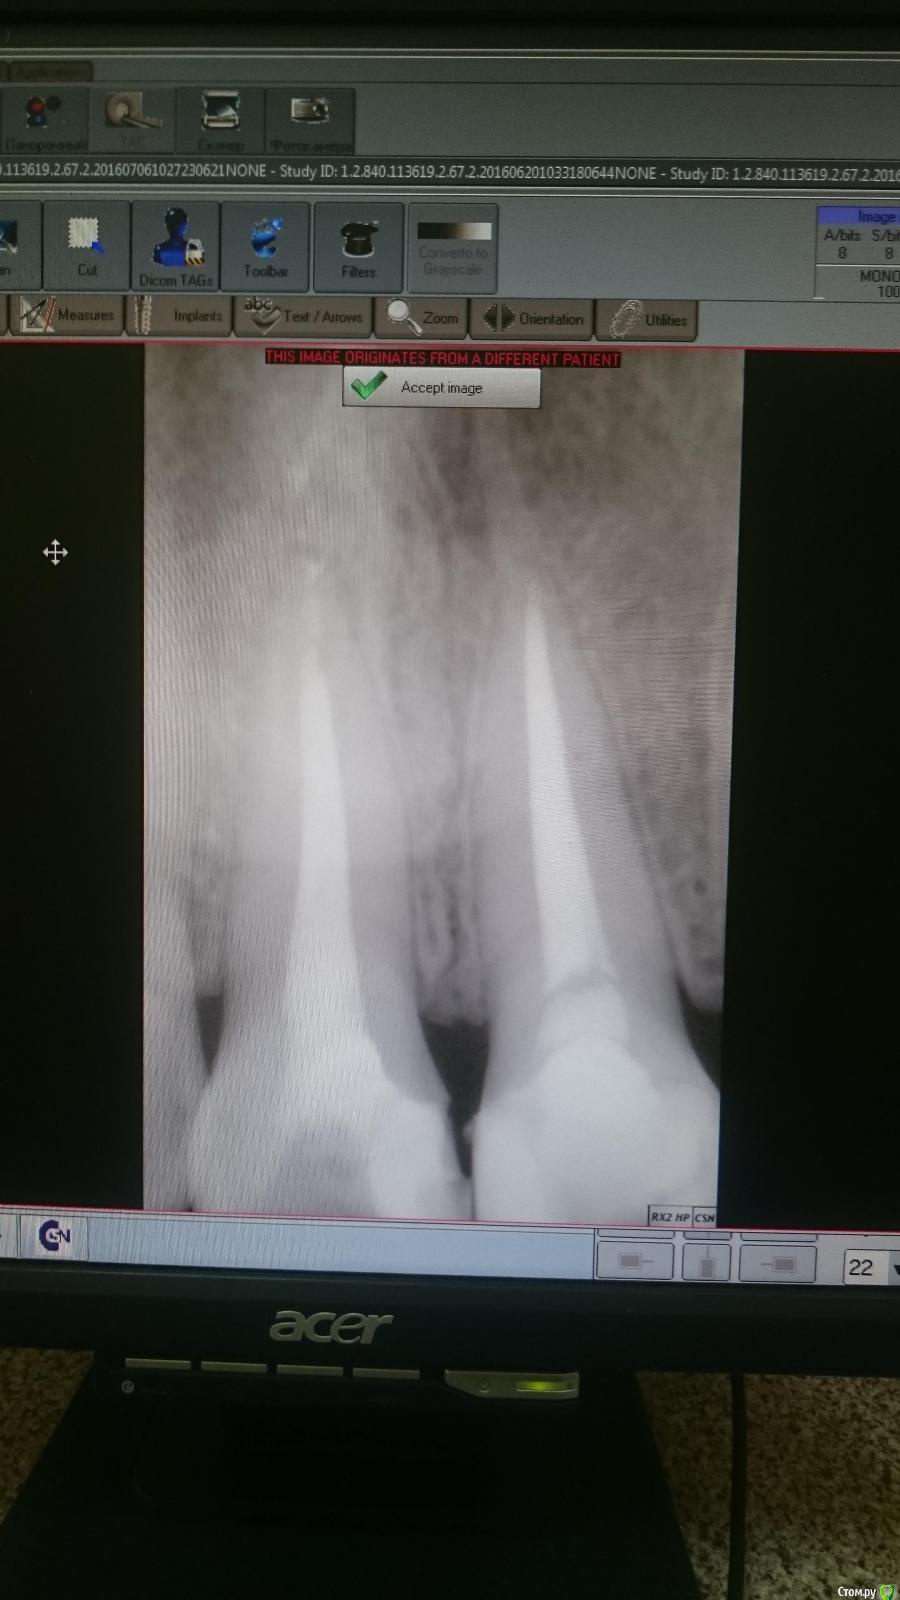

Есть два снимка (один и тот же зуб). Есть зуб, сверху него что-то темное.

На первом скриншоте зуб слева, на втором скриншоте зуб справа

post-48391-0-49250300-1467777335_thumb.jpg